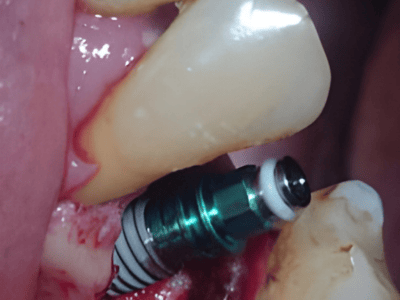

Dr. Deeksha Bhardwaj is a highly skilled dental specialist in Greater Noida, specializing in

Periodontics, Dental Implants, and Advanced Gum Care. With a BDS and MDS in Periodontics, she

provides expert treatment for gum diseases, receding gums, and dental implant procedures using the

latest technology.

Dr. Bhardwaj holds a BDS and MDS in Periodontics, specializing in gum health, dental implants, and advanced periodontal care.

Dr. Bhardwaj specializes in Periodontics, offering treatments for gum diseases, dental implants, laser dentistry, root canal treatments (RCT), teeth whitening, smile makeovers, and general dental care.